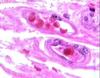

what is pictured

autonomic ganglia